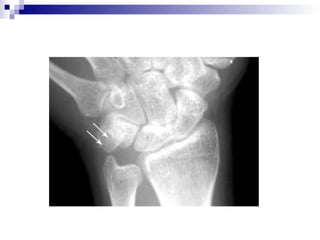

Colles kırığı:

 Distal radius metafiz kırığıdır.

 El üzerine düşme ile meydana gelir

 Radius dorsale deplase olur.

 El bileğinde karakteristik dorsifleksiyon veya çatal

sırtı deformitesi oluşur.

   AP grafide radius distal metafiz kırığı .

   Lat. grafi dorsal açılanmayı en iyi gösterir.

Colles kırığı